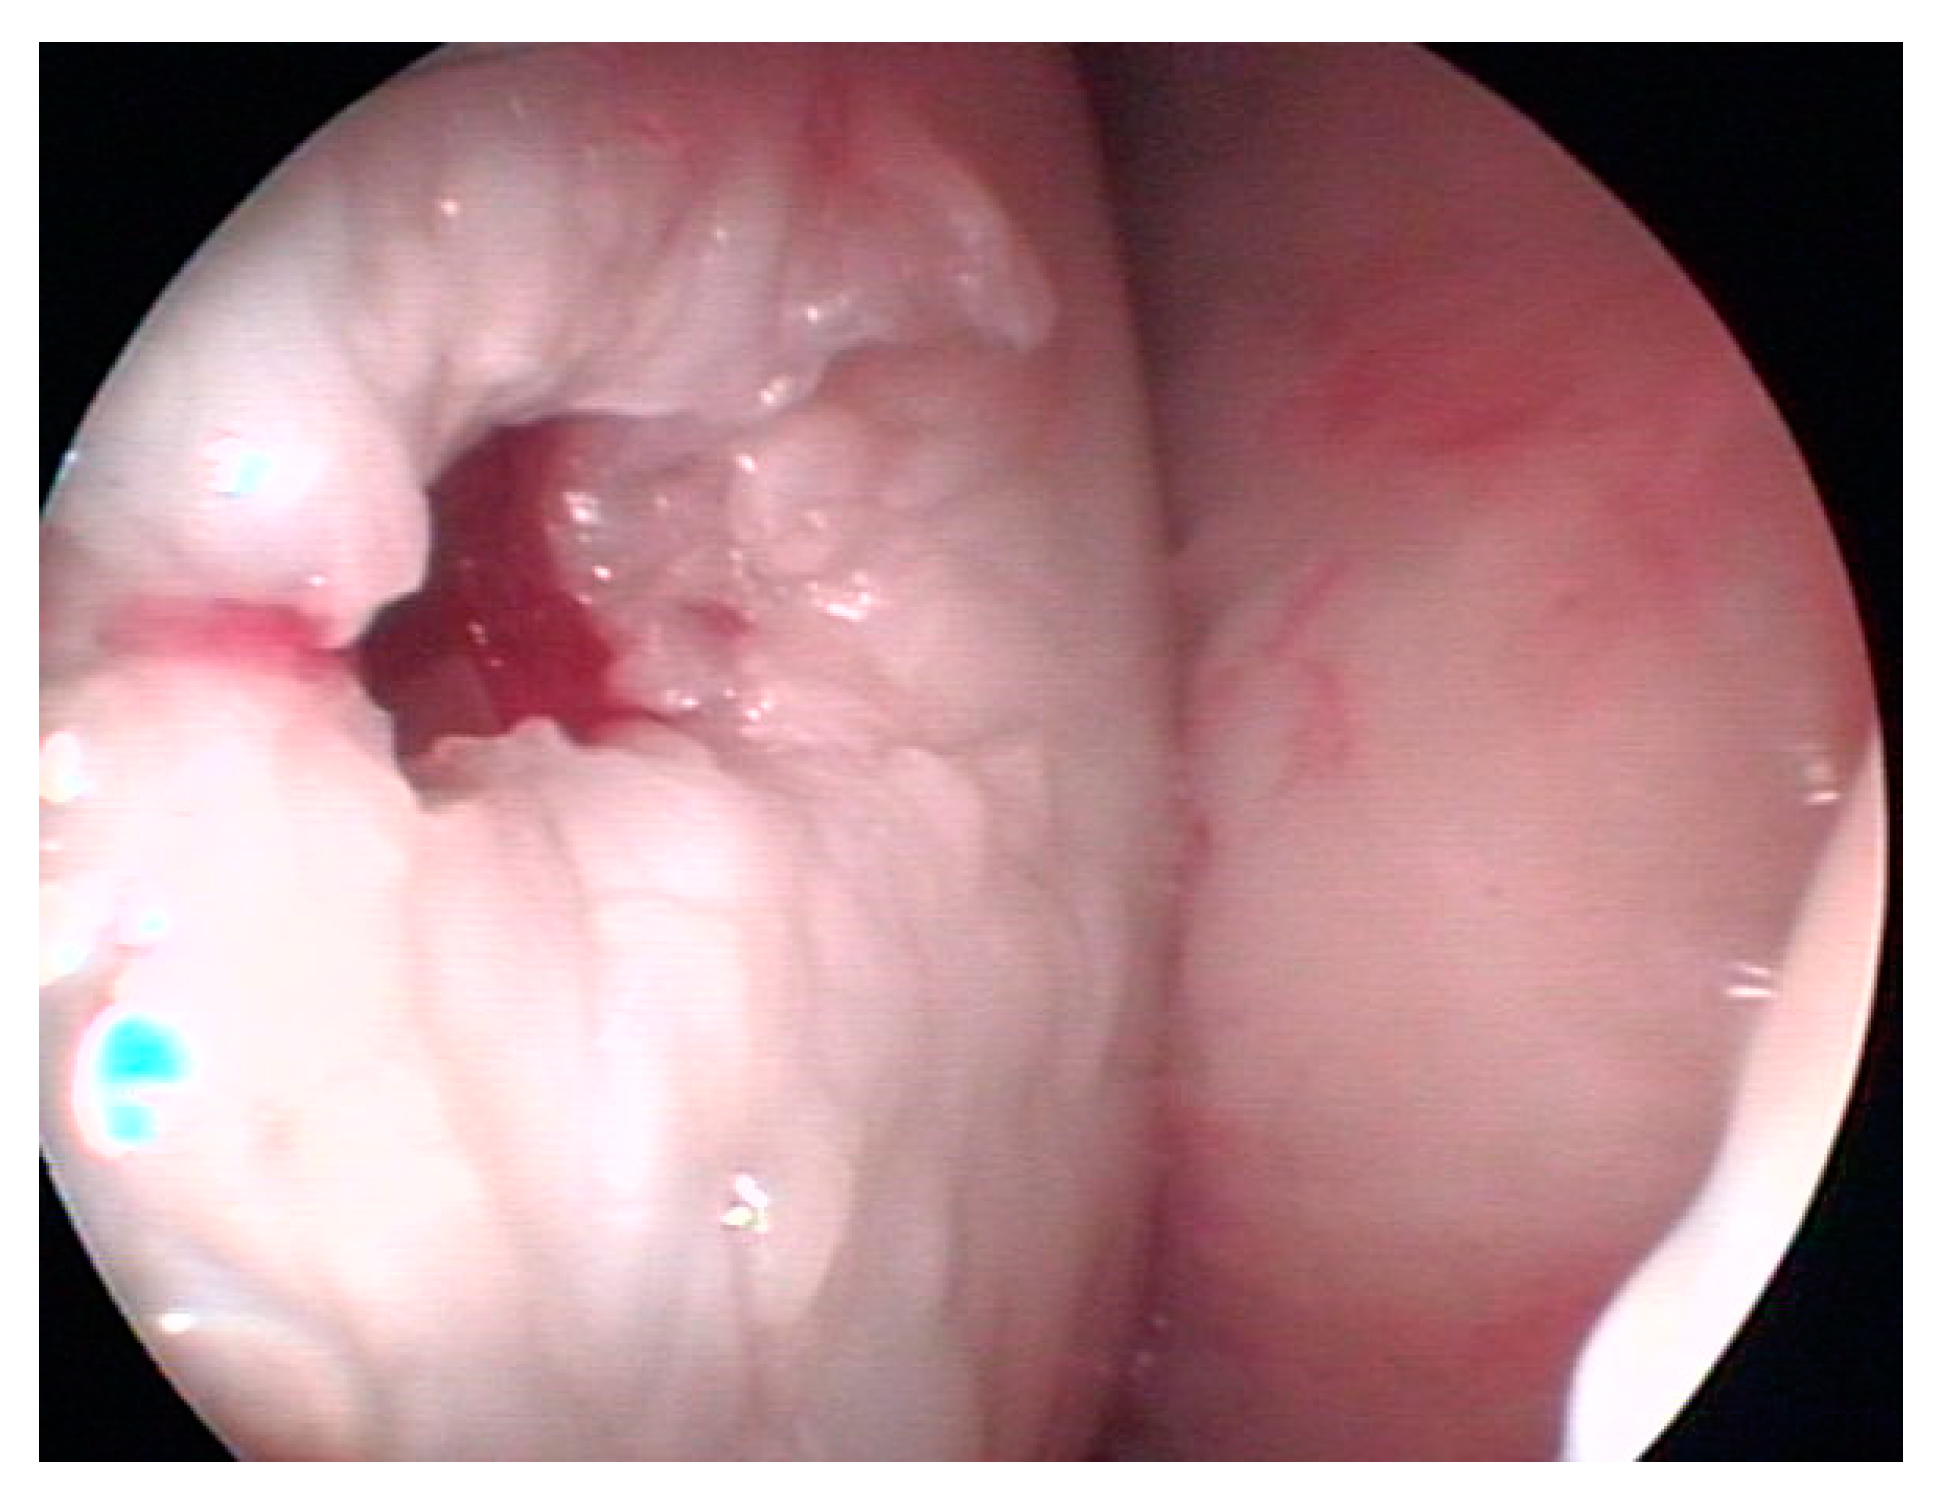

2.4. Surgical Treatment of the Clinical Case

3.1. Bone Cyst Treatment

3.2. Clinical Evaluation